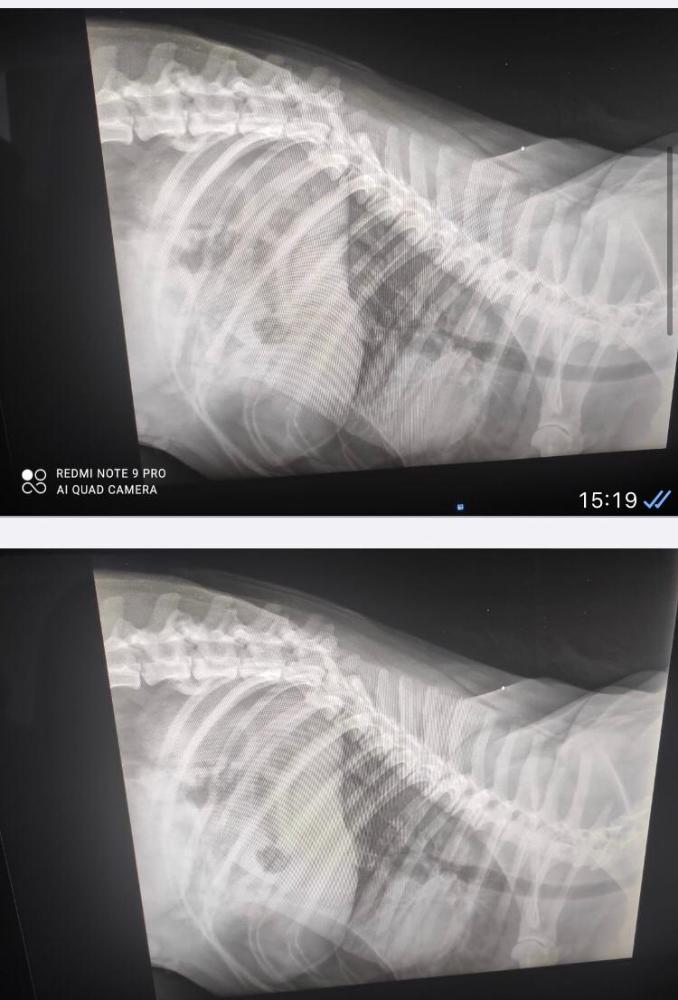

Анна2490 Опубликовано 10 мая, 2021 Опубликовано 10 мая, 2021 Друзья, тем, кто пока ещё не знаком с историей Грея, можно, пройдя по хэштегу, узнать все подробности. Но, в двух словах: три дня назад, собаку, которую кто-то привязал к дереву в наморднике, в чеховском районе, а потом отпустил - сбила машина. В результате - перелом позвоночника, множественные ушибы и оторванные рёбра. Было проведено несколько консультаций с ведущими врачами и поиск хирурга для проведения операции. В настоящий момент, Грей находится в ветеринарной клинике «Vet.city», в отделении реанимации. Сегодня состоялся консилиум врачей. Ситуация такова: нужно обязательно делать КТ/МРТ перед хирургическим вмешательством. А для этого нужен наркоз (не говоря уже о самой операции). Но, как показало ЭХО сердца, у Грея отмечается сердечная недостаточность - наркоз делать опасно. Поэтому, пока все силы направлены на стабилизацию организма и улучшение сердечной деятельности. Берутся дополнительные анализы. Это то, что касается состояния Грея. Но есть ещё новости! У него обнаружен чип и клеймо. Информация найдена: Грей - лабрадор ретривер, 7-ми лет. Хозяйка умерла полгода назад, в возрасте 58 лет. А теперь о главном! Объявлен ФИНАНСОВЫЙ СБОР! ? Грею очень нужна ваша помощь и финансовая поддержка! Характер повреждений таков, что операция будет очень дорогостоящей! Не говоря уже об обследованиях, пребывании в реанимационном отделении и последующей реабилитации! На данный момент:✔️собрано - 98.720✔️оплата стационара 07.05 и анализы - 2.500✔️предоплата в клинике «Vet.city” - 20.000 ✔️ остаток - 76.200 Предстоящие расходы: ✔️ операция - 100.000-150.000 ✔️ пребывание в отделении интенсивной терапии - 3.500-4.000 руб/сут (+ стоимость медикаментов)✔️ КТ/МРТ - 15.000✔️ анализы и обследования - 15.000-20.000 ✔️дальнейшая реабилитация - 30.000 ✅ Реквизиты помощи: 5228 6005 0319 7024 Карта Сбера на имя Кузнецов С.А. Кураторы: Елена Дворецкая/ Анна Кухарская #Грей_живи #сбитаясобакамолоди

alkor17 Опубликовано 16 мая, 2021 Опубликовано 16 мая, 2021 В ИГ пишут что были у Ягникова, его мнение - собака спинальник, потом отвезли в стационар ВетСити. Сбор в ИГ конечно идёт большой, судя по скринам. Сам профиль не особо информативен, как мне показалось. Сами понимаете спинальник это сбор бесконечный...